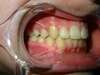

Intrabuccale face - Avant traitement 1 (12-04-2021) - 2

Intrabuccale face - Fin de traitement (10-06-2024) - 40